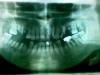

m4x Опубликовано 12 августа, 2011 Поделиться Опубликовано 12 августа, 2011 (изменено) Здравствуйте, уважаемые врачи ! Подскажите пожалуйста ! Хочу выровнять по возможности передние зубы... Это возможно ? Если да, то какое лечение показано(нижние передние все с кариесом) ? Прорезировать хочу на импланты. Ортопед говорит : "Так пойдет !" Может хотя бы сделать 3D моделирование с учетом возможного последующего прорезирования на импланты еще имеющихся зубов но в ровной форме ? Поделитесь своим мнением о моей ситуации, пожалуйста ! Большое спасибо всем за комментарии и ответы ! Изменено 12 августа, 2011 пользователем m4x Ссылка на комментарий